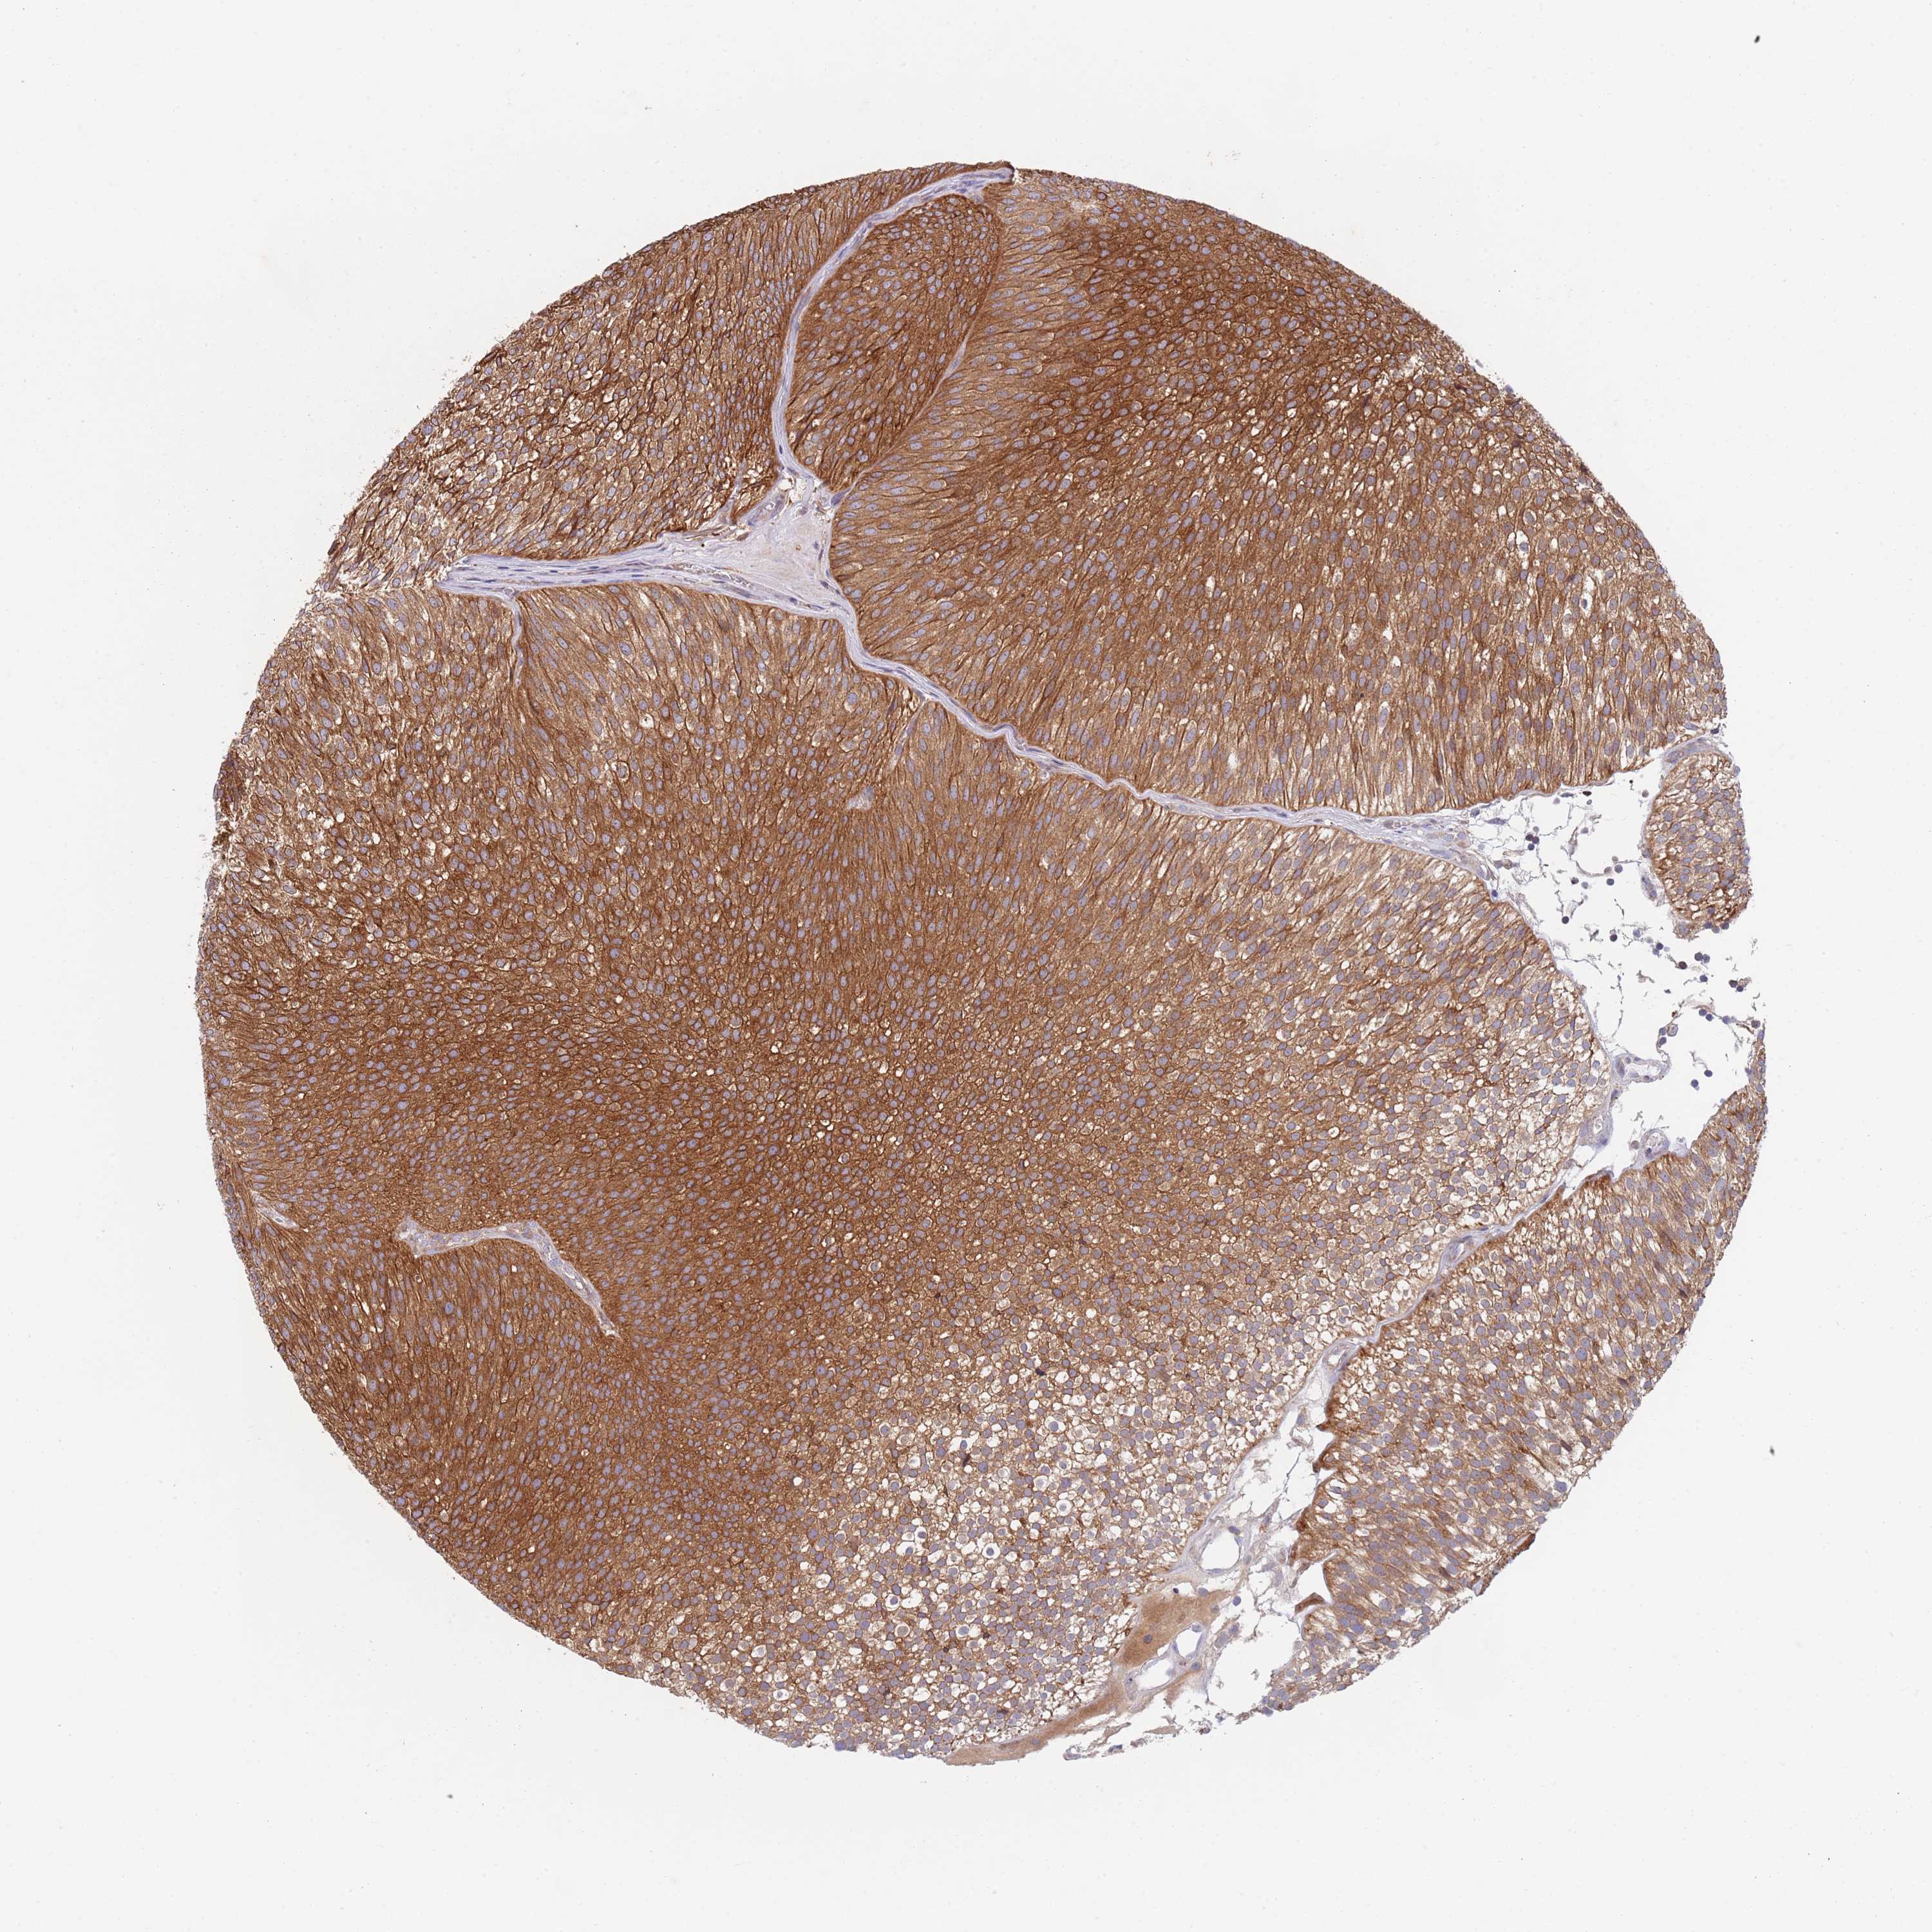

UROTHELIAL CANCER - Protein expressioni

A mouse-over function shows sample information and annotation data. Click on an image to view it in a full screen mode. Samples can be filtered based on level of antibody staining by selecting one or several of the following categories: high, medium, low and not detected. The assay and annotation is described here.

Note that samples used for immunohistochemistry by the Human Protein Atlas do not correspond to samples in the TCGA dataset.

Antibody stainingi

Antibody staining in the annotated cell types in the current human tissue is reported as not detected, low, medium, or high, based on conventional immunohistochemistry profiling in selected tissues. This score is based on the combination of the staining intensity and fraction of stained cells.

Each image is clickable and will lead to virtual microscopy that enables deeper exploration of all samples and also displays staining intensity scores, fraction scores and subcellular localization as well as patient and tissue information for each sample.

Antibody HPA020879

Staining

High

Medium

Low

Not detected

Intensity

Strong

Moderate

Weak

Negative

Quantity

>75%

75%-25%

<25%

None

Location

Nuclear

Cytoplasmic/membranous

Cytoplasmic/membranous,nuclear

Urothelial carcinoma, Low grade

Urothelial carcinoma, High grade

Urothelial carcinoma, NOS